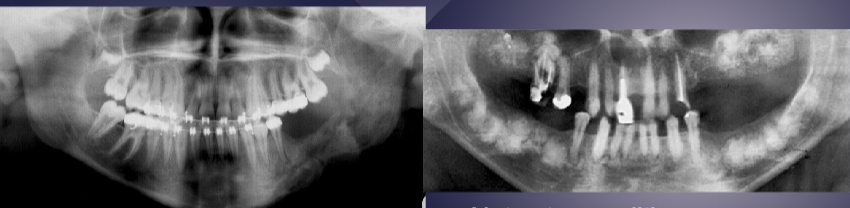

differentiate the pathology of the 2 images

left: loss of apical lamina dura + periapical radiolucency

right: normal lamina dura + radiolucency due to submandibular fossa